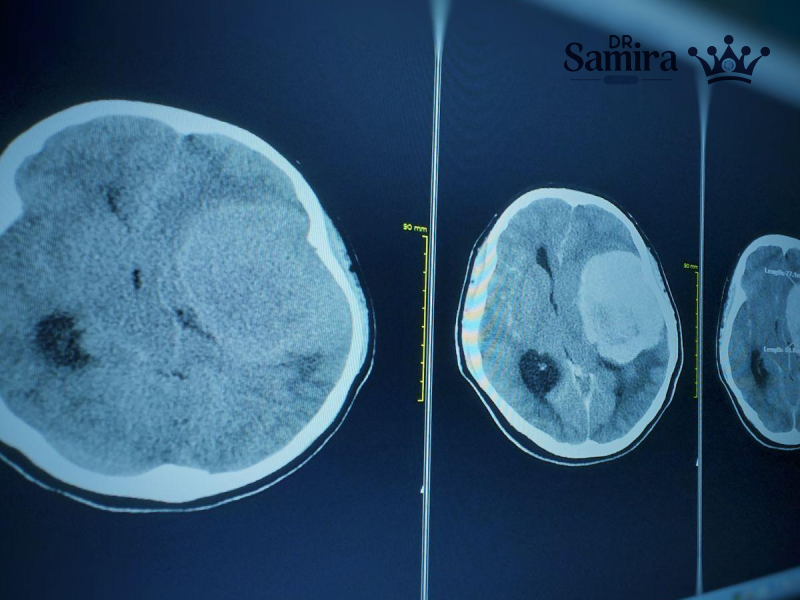

مننژیوم گرید یک یکی از شایع ترین تومورهای مغزی با منشا سلول های مننژ است که...

مننژیوم گرید ۳ یکی از تهاجمی ترین انواع تومورهای مغزی است که تحت عنوان مننژیوم آناپلاستیک...

مننژیوم آتیپیک یا گرید دو (Atypical Meningioma) یکی از انواع تومورهای سیستم عصبی مرکزی است که...